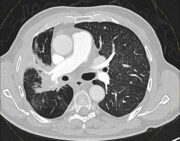

Lungenkrebs: Höhere Strahlendosis ist sicher und vielversprechend

Eine Studie von Forschenden der Karl Landsteiner Privatuniversität für Gesundheitswissenschaften in Krems (Österreich) zeigt, dass eine intensivere Strahlentherapie bei Lungenkrebs das Risiko für entzündliche Reaktionen nicht erhöht, aber möglicherweise die Überlebenschancen verbessert.

Strahlentherapie bei Lungenkrebs: „Orphan Drug“ könnte die Wirksamkeit erhöhen

Ein von der FDA als „Orphan Drug“ ausgewiesenes Medikament, das auf eine zentrale Schwachstelle bei Lungenkrebs abzielt, hat sich in einer Studie von Forschenden des University of Texas (UT) Southwestern Medical Center (USA) in Bezug auf die Verbesserung der Wirksamkeit einer Strahlentherapie in präklinischen Modellen als vielversprechend erwiesen.